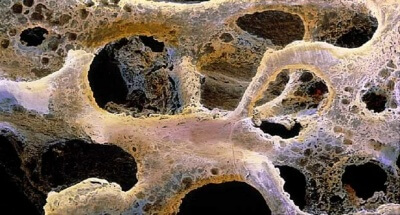

Костно-пластические материалы для имплантологии: подробный обзор